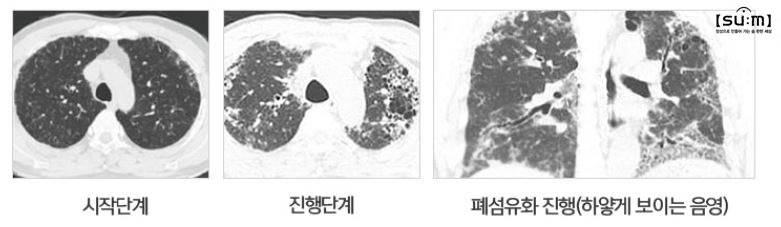

폐 단면을 확인하는 검사인 흉부 CT, 폐 용적을 검사하는 폐기능 검사를 비롯하여 호흡곤란 정도를 측정하기 위한 산소포화도, 중증으로 진행될 경우 더욱 심층적 검사인 동맥혈 산소 검사 등을 통해 폐섬유화 상태를 판단할 수 있다. 이런 치료에 앞서 무엇보다 중요한 점은 CT, X-ray 등의 영상학적 검사를 통해 단편적으로 질환을 해석하는 것이 아닌 병증 진행의 전후 관계와 현재 체력 상태, 검사상 해석을 종합적으로 판단하여 치료에 임하는 것이다.